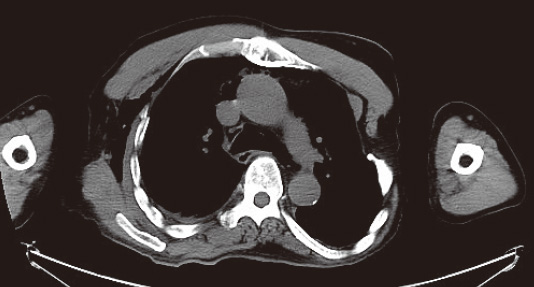

肩関節病変、上腕骨骨折、股関節、腕おろし体幹部撮影など、ストリークアーチファクトの発生しやすい条件下において、HDCTはアーチファクトの影響が軽減され、画質が向上し、有用性のある装置であることが確認できた。図6、7に、HDCTが有用であった症例画像を提示する。

図7  腕おろし体幹部症例 両腕挙上が不可能な方の胸部撮影